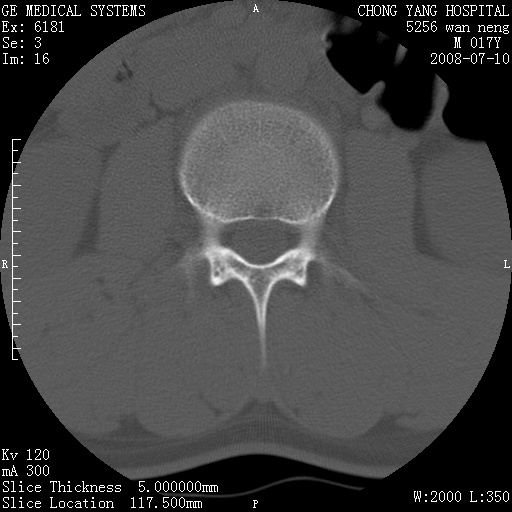

腰3、4椎弓崩裂

腰3、4椎弓不连

支持:腰3、4椎弓峡部崩裂。

腰3、4椎弓峡部不连

支持:腰3、4椎弓峡部崩解。

图片漂亮,目前也只能看到腰3、4骨质不连

腰3、4椎弓峡部裂。

腰3、4椎弓峡部裂。支持

重建图像见多个椎弓峡部不连(不足为据),平扫未见异常。

支持腰3、4椎弓峡部崩裂。